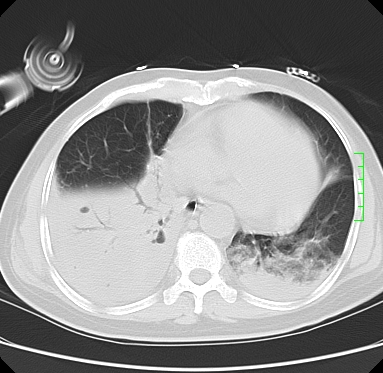

icu病人,几天都没明确诊断。m,76y,咳嗽、咳痰1周,伴气促,右胸痛入院,pe:t38.3c p135 r25 bp135/85。双肺可闻及大量湿罗音,心、腹未见明显异常。诊断:1心衰?2肺部感染?3冠心病?

9号平片

11号ct

双肺感染性病变,下叶膨胀不全,胸水,左室大。

1)两肺感染性病变(右肺下叶肺脓肿可能)。2)双侧胸腔积液,以右侧为甚。

ards,肺感染性病变,右下叶实变,双侧胸腔积液,右侧为著,叶间胸膜积液,右上肺陈旧性tb纤维灶,左室大。